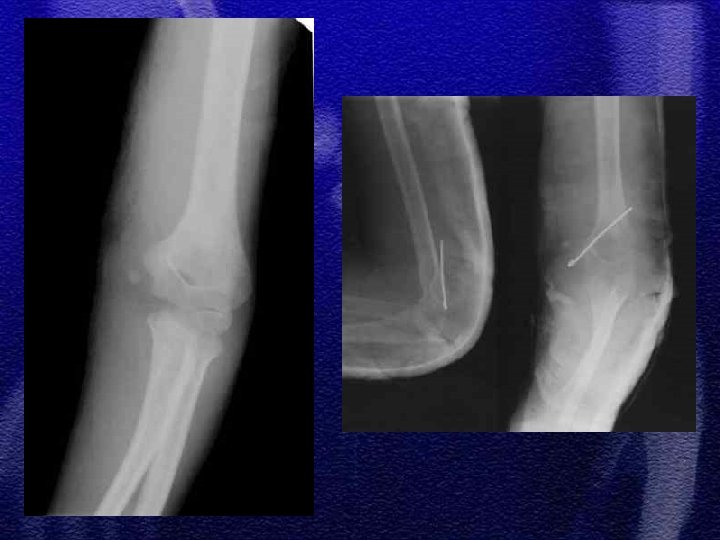

§ Repozycja zamknięta , unieruchomienie gipsowe § Repozycja zamknięta i zespolenie przezskórne dwoma drutami Kirschnera § Repozycja otwarta i zespolenie dwoma drutami Kirschnera skrzyżowanymi lub równoległymi § Wyciąg szkieletowy typu „Zeno”

§ Wyprostne - 95% § Zgięciowe - 5% § Klasyfikacja wg Gartlanda

1. Szczyt występowania złamania 3 -10 rok życia, co wynika z budowy anatomicznej, która predysponuje do ww. złamań 2. Wiotkość torebki stawowej i więzadeł usposabia do przeprostu 3. Linia złamania przebiega w przynasadzie w miejscu jej ścieńczenia (dół dla wyrostka dziobiastego oraz wyrostka łokciowego )